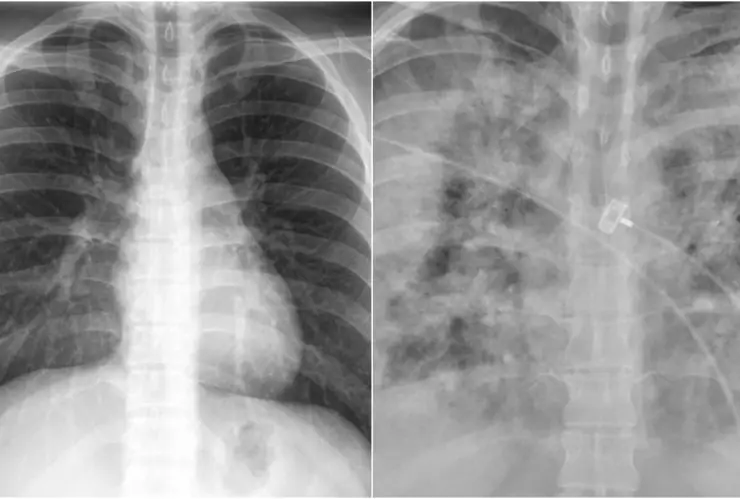

Faheem Younus, jefe del departamento de enfermedades infecciosas de la Universidad de Maryland, realizó una comparación con radiografías de pulmones de las personas no vacunadas contra las que sí se inyectaron contra el Covid-19.

En las imágenes que compartió en su cuenta de Twitter, Faheem Younus explicó que con la vacuna de Covid-19 se puede contraer la enfermedad, sin embargo, esta es generalmente leve, en comparación de las personas no vacunadas, que incluso llegan a la Unidad de Cuidados Intensivos (UCI).

Con la radiografía de los pulmones de personas no vacunadas y las que sí, el científico busca generar conciencia en la población para que se vacune, ya que puede ser la diferencia entre salvar la vida y no.

With Without

Vaccination Vaccination pic.twitter.com/GIcb5mJQz9